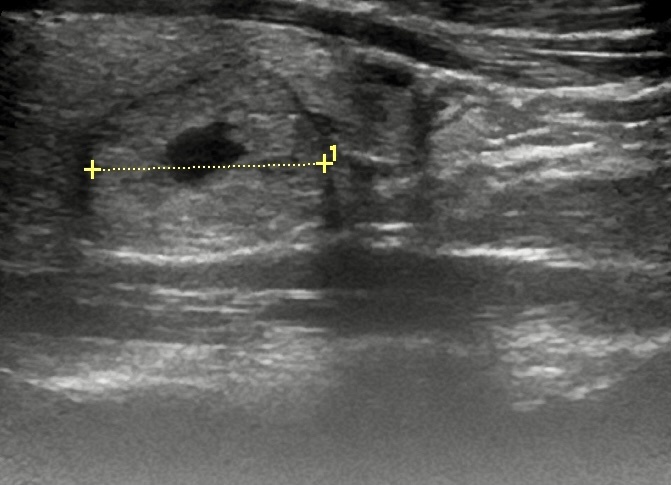

В заключении доктора УЗИ был указан размер узла 5 см, а объём доли, в которой его обнаружили, был не увеличен. Пальпаторно эндокринолог также не прощупывала крупные узлы.

Принципиальность оценки размера в этом случае была обусловлена еще тем, что узлы, достигающие 5 см и более, даже при доброкачественной природе требуют хирургического вмешательства.

Узел щитовидной железы

Я выполнила новое УЗИ щитовидной железы пациентке. Размер узла действительно оказался меньше на 2см; он был около 3см. При таком размере в случае отсутствия злокачественных клеток в биоптате рекомендуется лишь динамическое наблюдение.